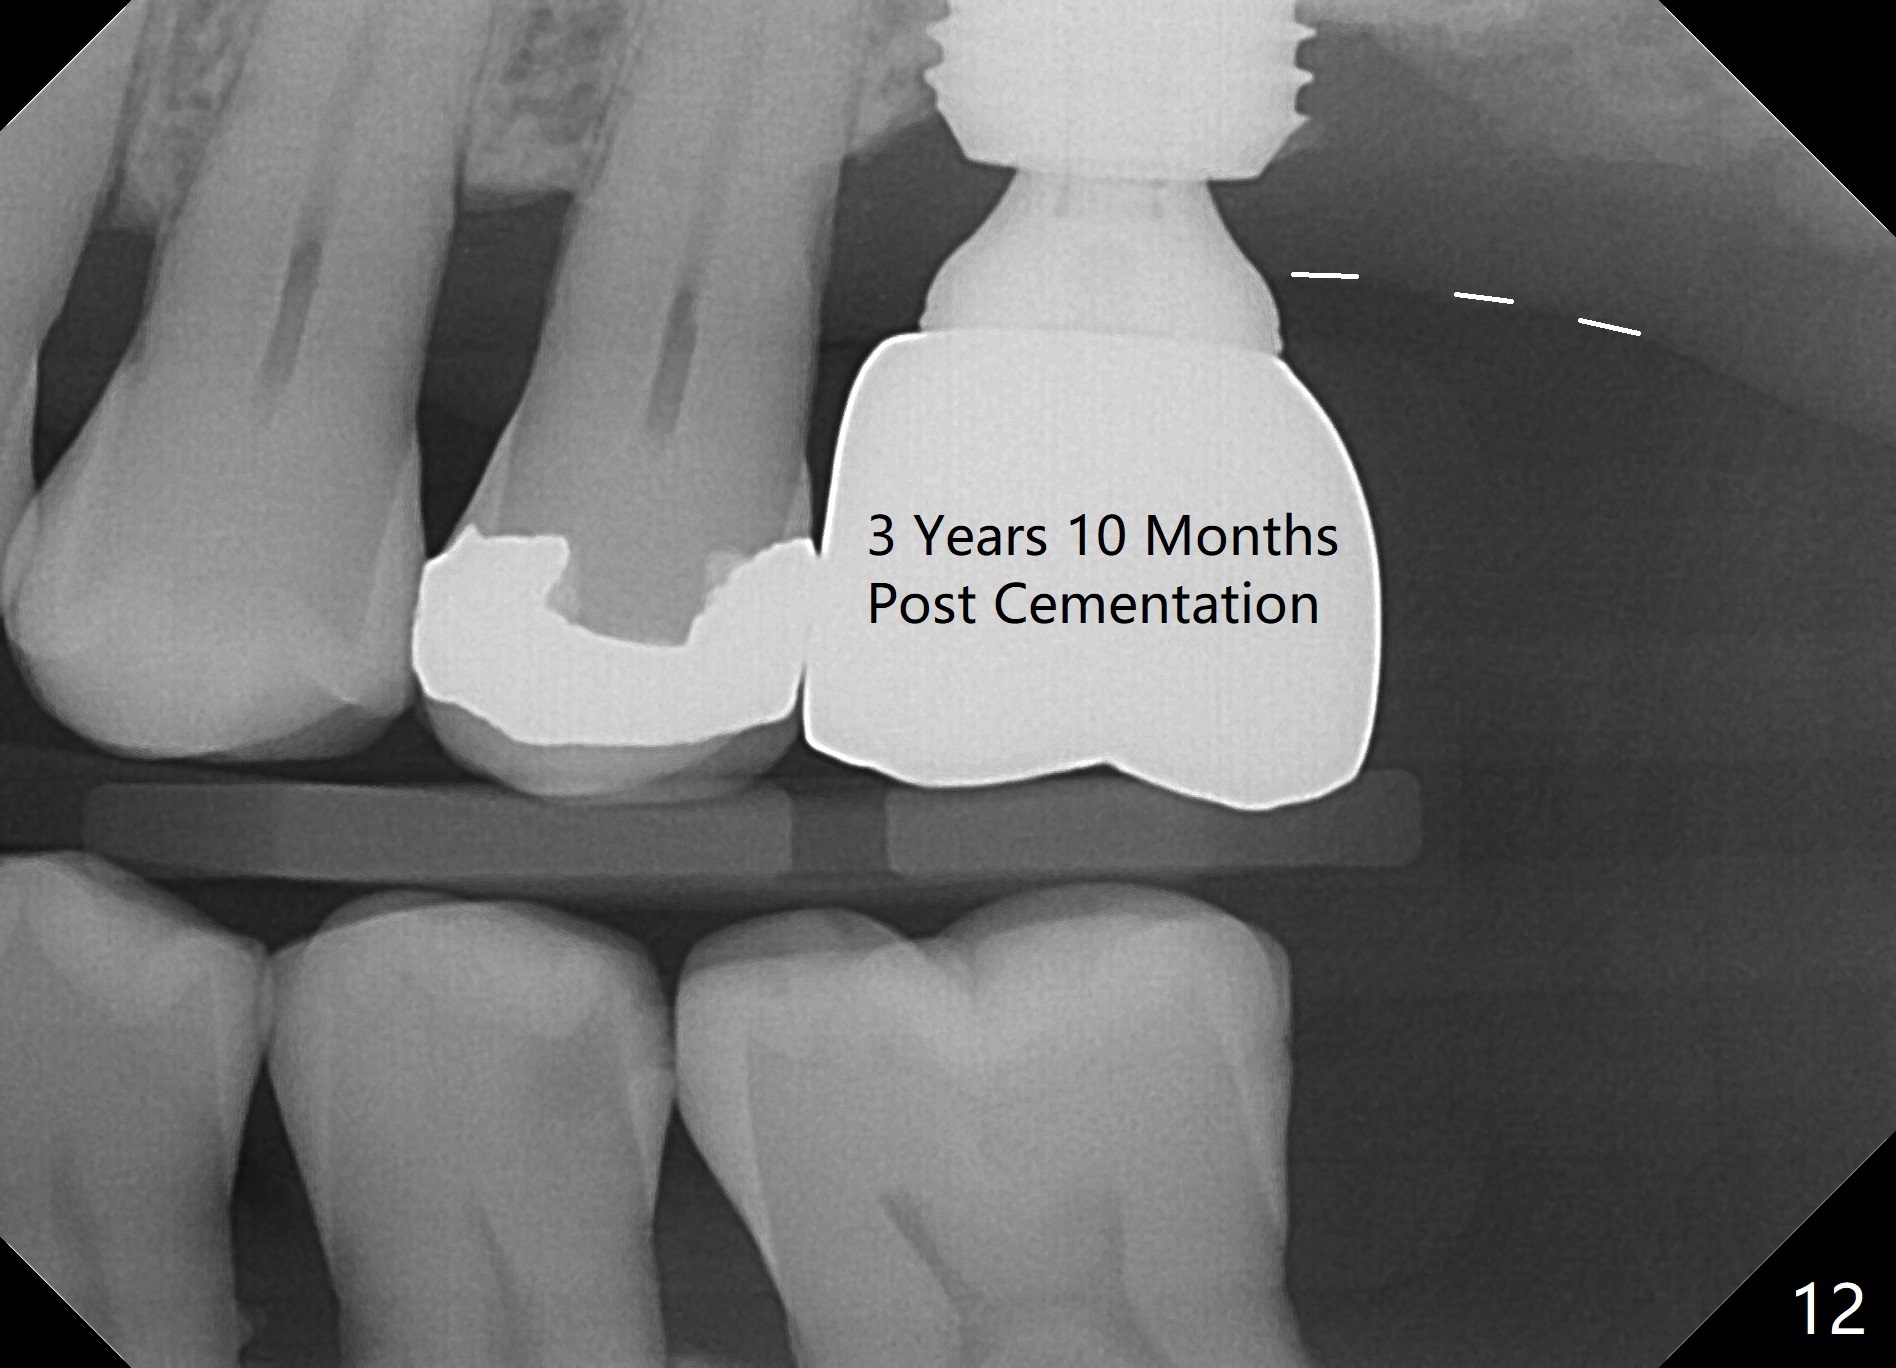

When the patient returns for impression 6.5 months postop, the provisional has dislodged because of the short abutment (Fig.7 A (6.5x4(2) mm). A longer one is placed (6.5x5(3) mm). When he returns for crown cementation 8.5 months postop, the provisional is retentive. The distal implant plateau is still exposed. Post-cementation panoramus shows that the distal 3 threads are not covered by the bone and that the crown/implant ratio is 5:3 (Fig.8). Implants are recommended at #3 and 30 (Fig.9). There is a distinct layer of bone apical to the implant at #14 22 months post cementation (Fig.10 *). In spite of exposure of 2-3 threads distally, there is no sign of peri-implantitis. It appears that the implant is subgingival (Fig.11 (BW) white dashed line: gingival margin). The implant remains infection free 3 years 10 months post cementation (Fig.12) due to the thick gingiva and good oral hygiene.